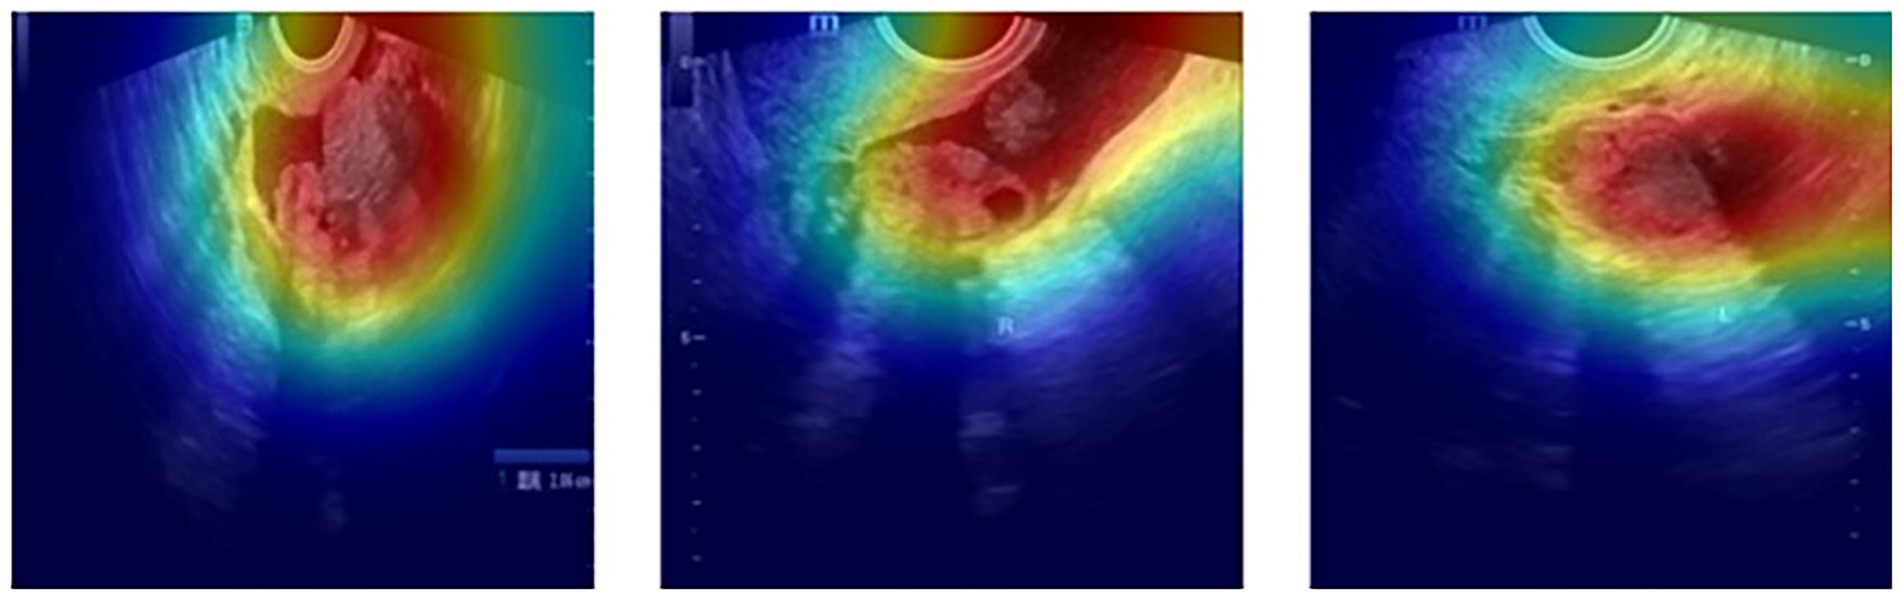

Qualitative evaluation of the generated activation maps was performed by overlaying these maps onto the original ultrasound images using OpenCV and PIL libraries. An activation threshold of 50% of the maximum value was applied to emphasize the regions identified by the models visually. Figure 3 provides representative examples of these Grad-CAM activation maps, clearly illustrating how the hybrid EfficientNetB7–Swin Transformer model effectively focuses on tumor-associated anatomical regions, aligning closely with clinical expertise and expectations.

Figure 3. Representative Grad-CAM activation maps of ovarian tumor ultrasound images. Activation heatmaps (red and yellow areas indicating higher activation) generated by the hybrid EfficientNetB7–Swin Transformer model overlaid onto original ultrasound images. These activation maps visually confirm that the model accurately focuses on clinically relevant tumor regions, thus reinforcing the interpretability and diagnostic credibility of the proposed hybrid architecture.

Visual examination of these maps confirms that model attention is consistently directed toward regions considered clinically significant by experts, reinforcing the interpretability and credibility of the hybrid CNN-Transformer approach in a clinical context. This interpretability facilitates trust in automated diagnostic decisions and represents a critical step towards the practical clinical adoption of artificial intelligence systems.